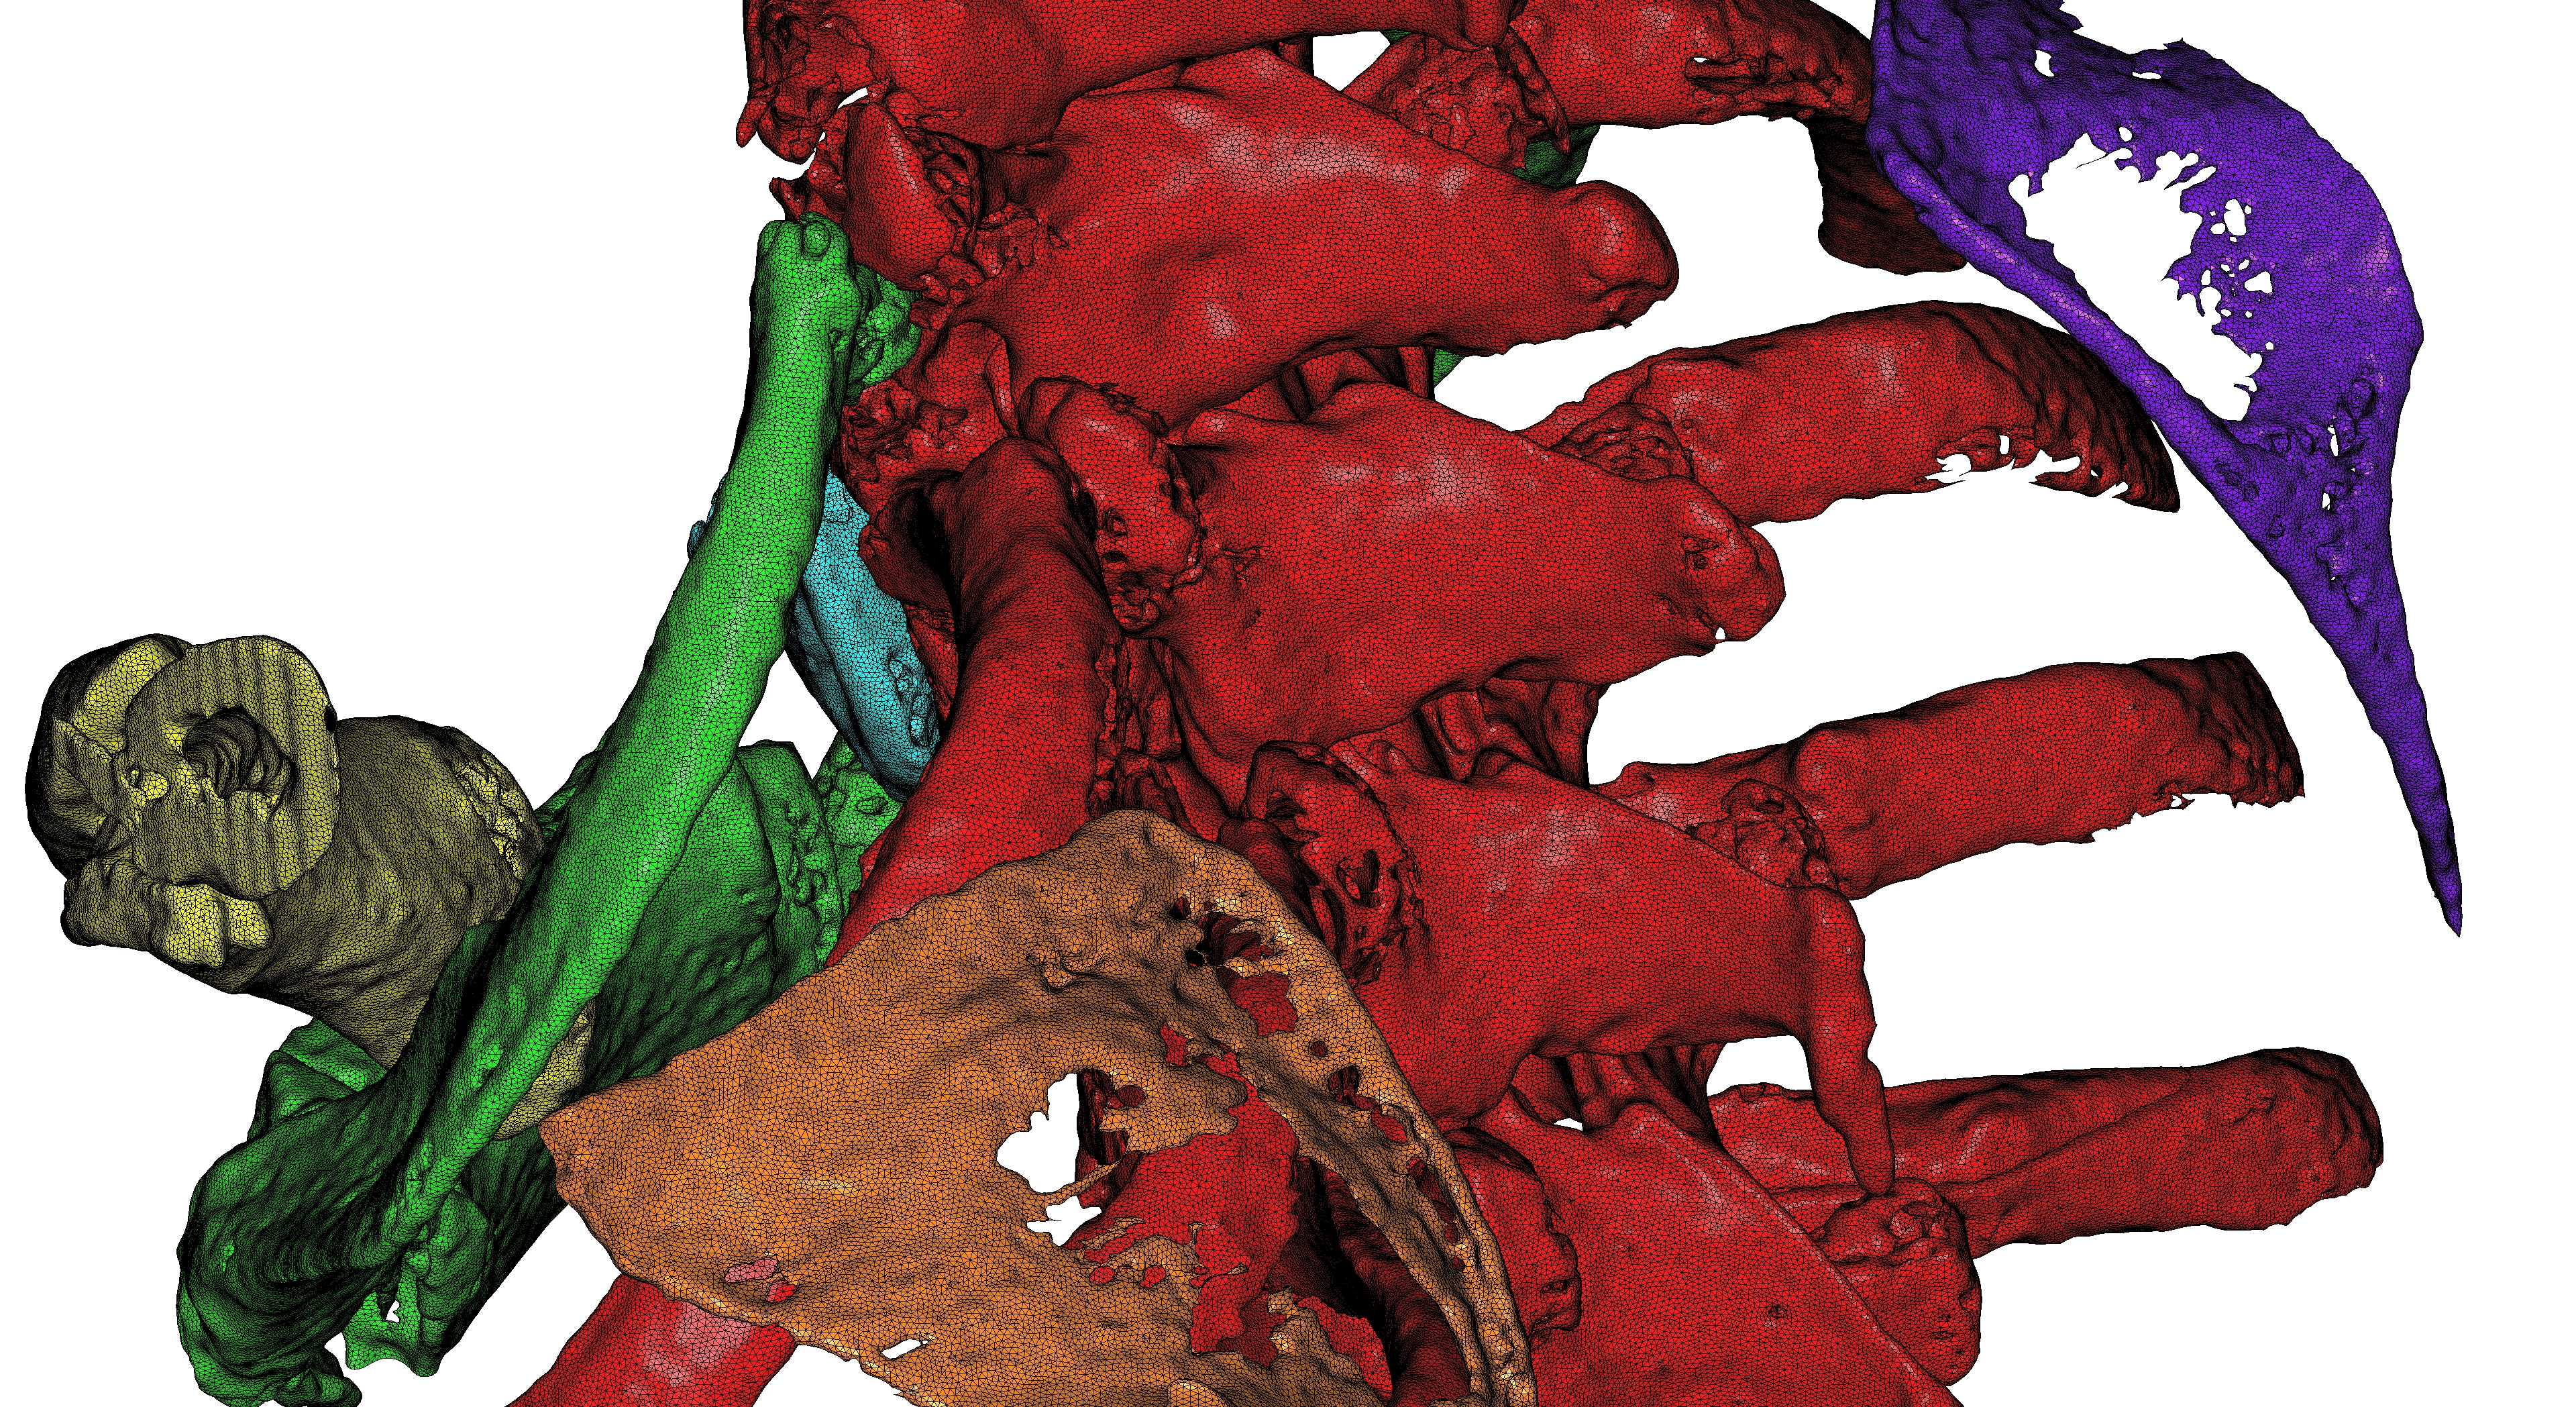

This example concerns MRI images. This is a complex model with 899 images of resolution (512,512).

For this model we are interested in the gray level = 100 and the 16 principal connected components.

Figure 1 shows the corresponding 3D model, containing 3,344,714 vertices and 6,705,955 triangles and 14,996 boundary edges, produced in 48.68 seconds and occupying 3,886 Giga-bytes in memory.